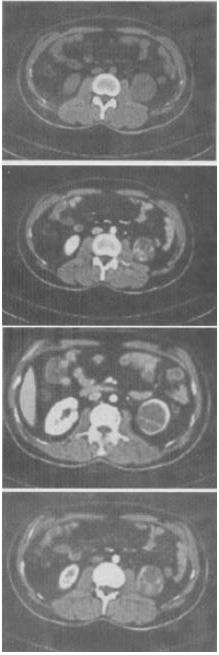

女,63岁,左腰部隐痛不适1个月余,CT平扫+增强如图所示,最可能的诊断是()。

A、左肾下极囊肿

B、左肾下极错构瘤

C、左肾下极癌

D、左肾下极脓肿

E、左肾下极淋巴瘤

C